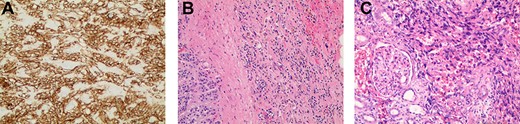

First appearance of multiple liver lesions suspicious for metastasis in transverse (left) and coronal (right) planes on CT; reduction of retroperitoneal effusion can also be seen.

Serial CT scans at 10 and 12 weeks post-resection revealed reduction of the retroperitoneal abscess and appearance of liver lesions concerning for metastasis (Fig. 4). The patient eventually completed his radiation course with no additional problems.